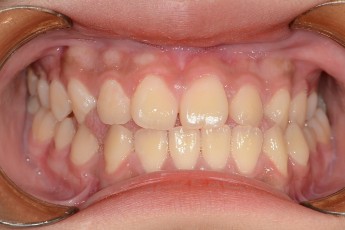

BEFORE & AFTER

- 덧니교정